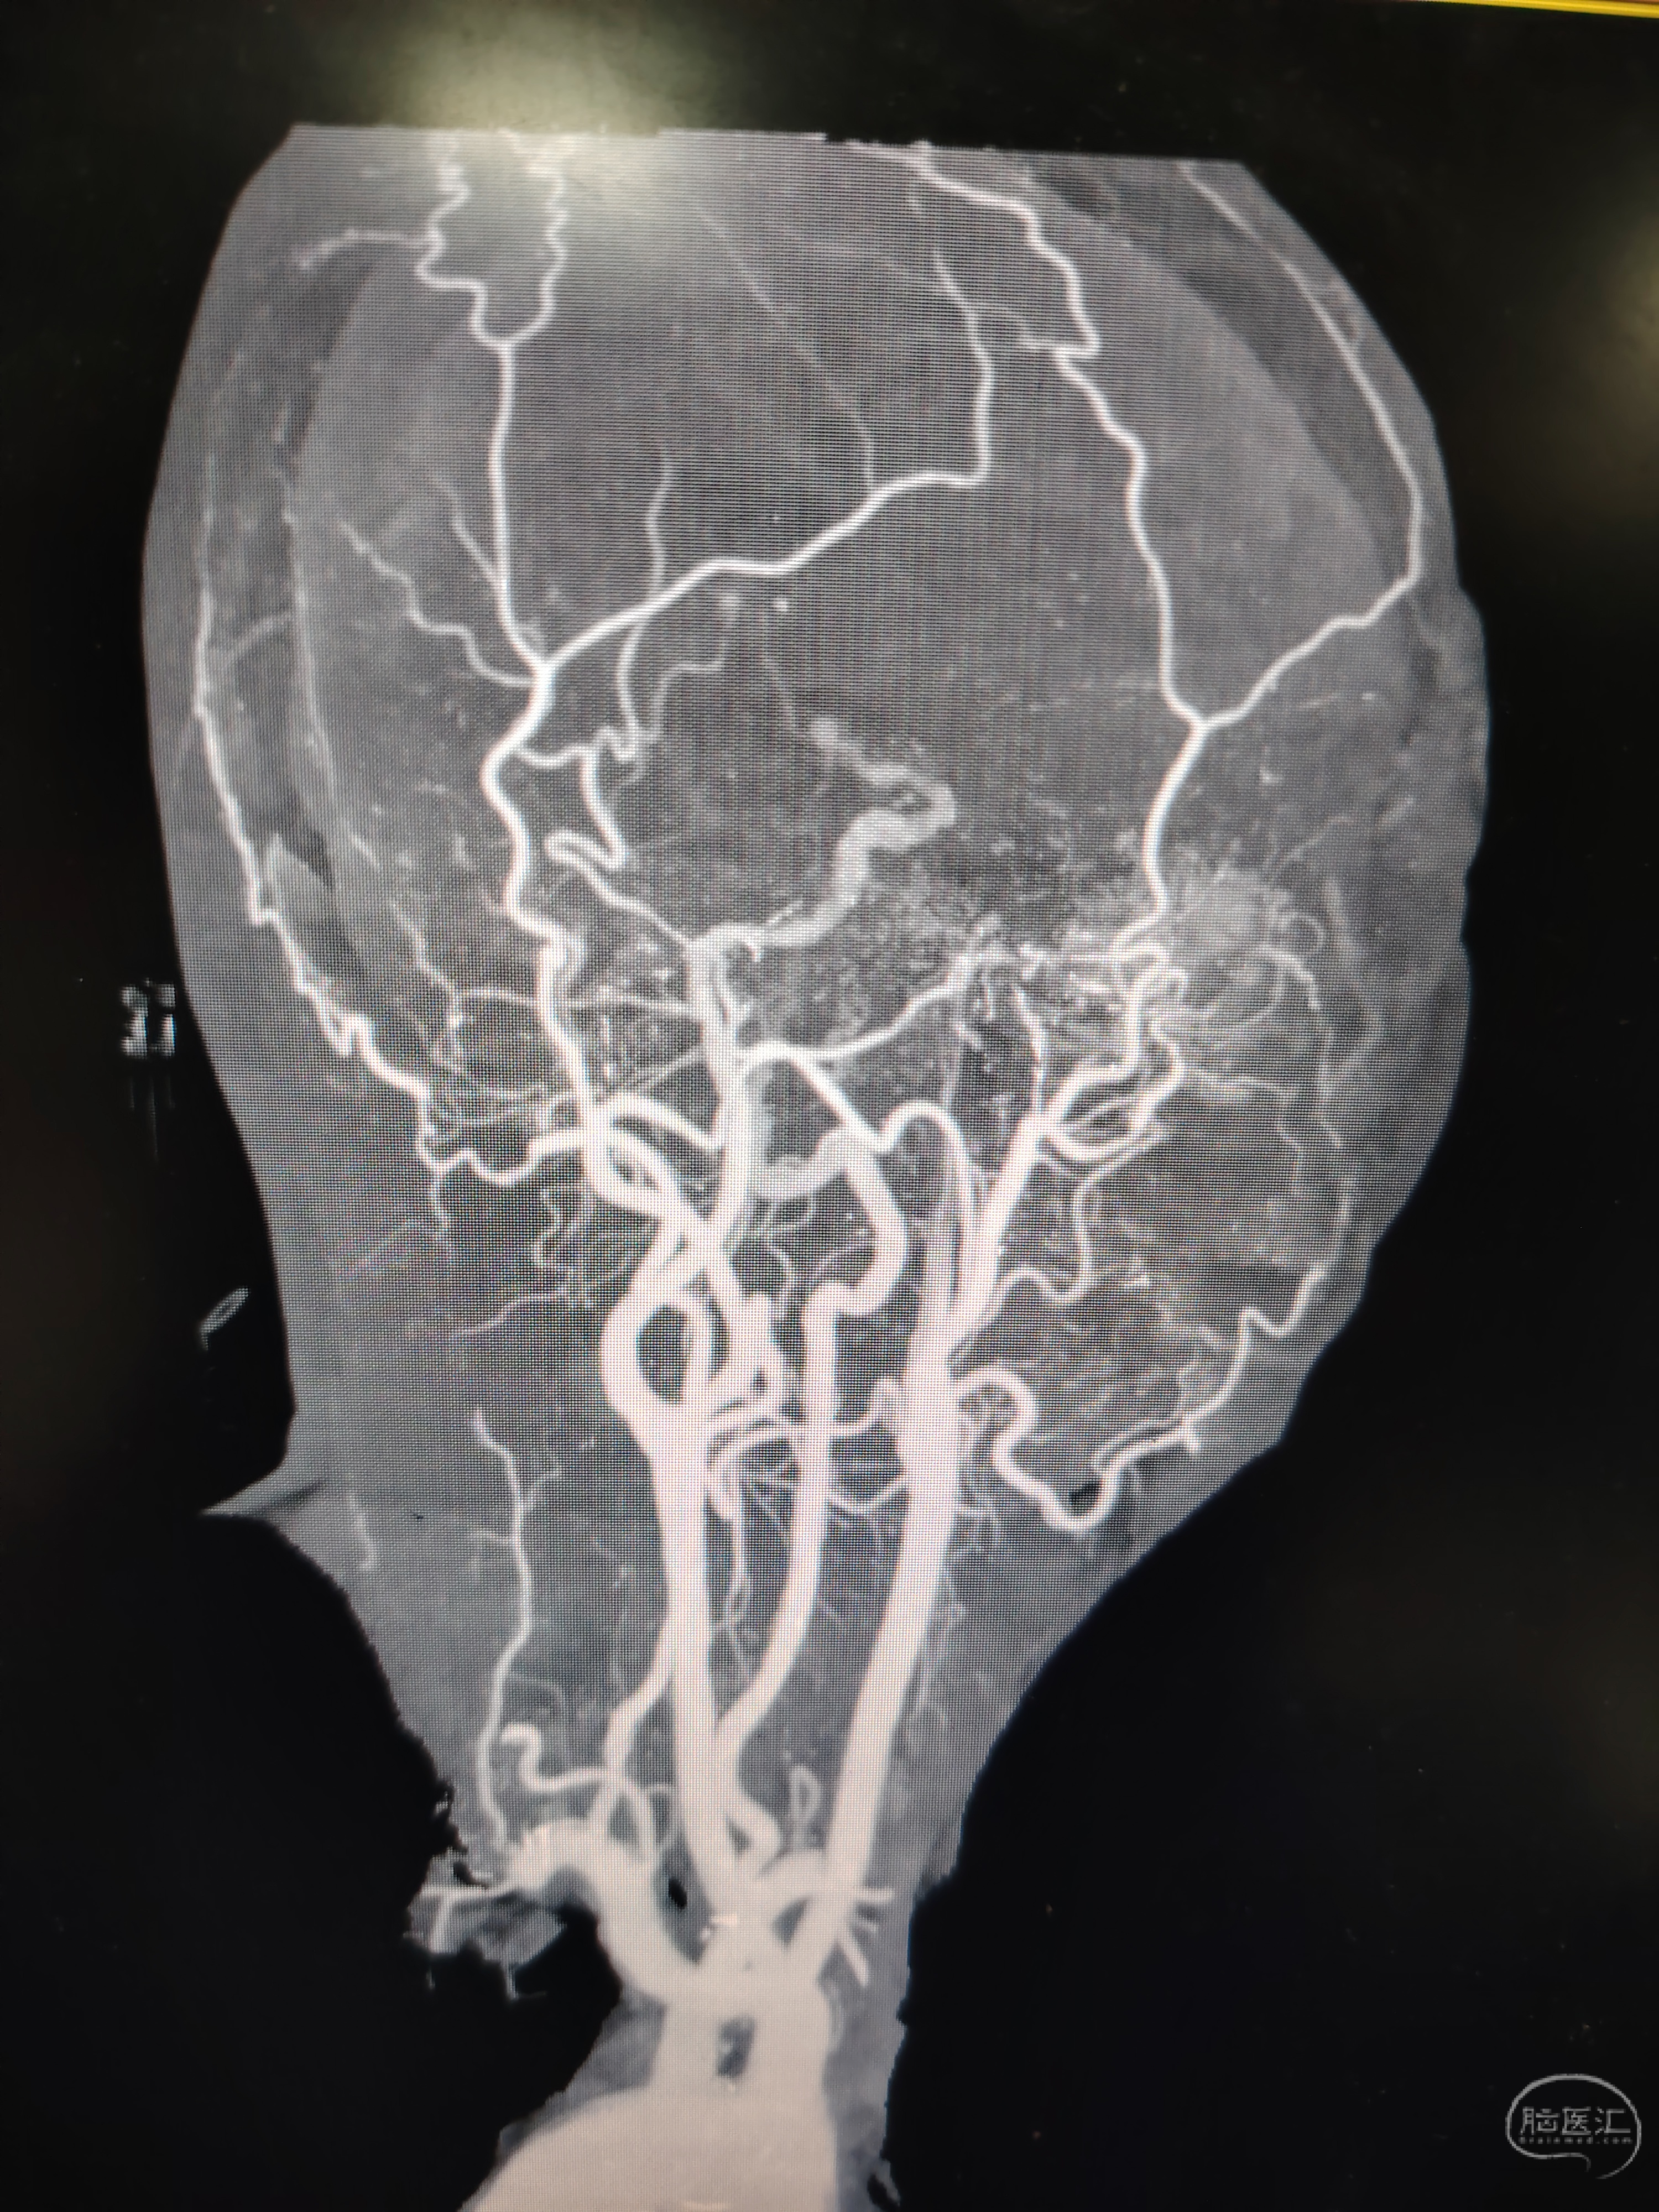

发病前MRA示颅内多发动脉瘤。

急症CTA颅内血管不显影。